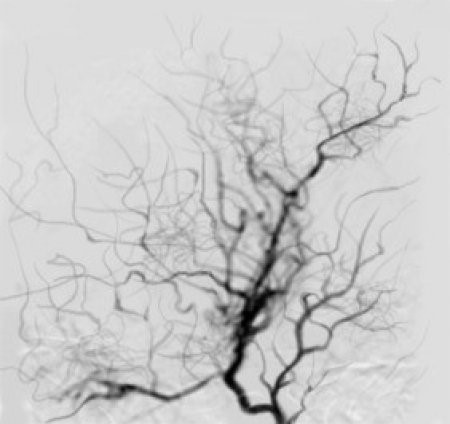

모야모야는 일본어로 ‘담배연기가 모락모락 올라가는 모양’을 뜻한다. 모야모야병은 일본의 의학자 스즈끼(Suzuki)에 의해 1969년 명명됐다. 모야모야병은 동맥 부분의 협착이나 혈관에 이상이 나타나 동맥 안쪽의 막인 동맥내막이 점차 두꺼워지는 증상을 동반한다.

모야모야병 증상은 소아의 경우 흔히 1~2시간 이내에 혈관이 딱딱해져서 일시적으로 한쪽 팔다리에 마비 증상이 나타나며 저리거나 운동기능이 마비되고, 발음에 장애가 생기며(발음부전) 시력이 저하되는 일과성 허혈발작이 나타난다.